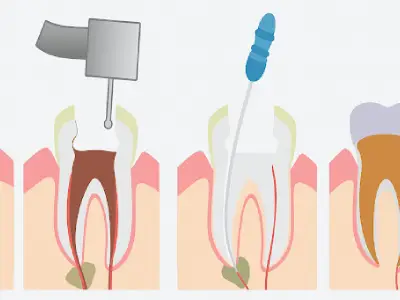

כתר הוא כמו "כובע" מגן שמכסה את השן כולה ומחזיר לה את הצורה, החוזק והמראה הטבעיים. אנחנו משתמשים בכתרים כדי להציל שיניים שנפגעו מעששת עמוקה, נשברו בתאונה, או נחלשו לאחר טיפול שורש.

שן שעברה טיפול שורש נחלשת ועלולה להישבר. כתר Emax מגן עליה ונותן לה חוזק חדש.

שן שעברה טיפול שורש נחלשת ועלולה להישבר. כתר Emax מגן עליה ונותן לה חוזק חדש.